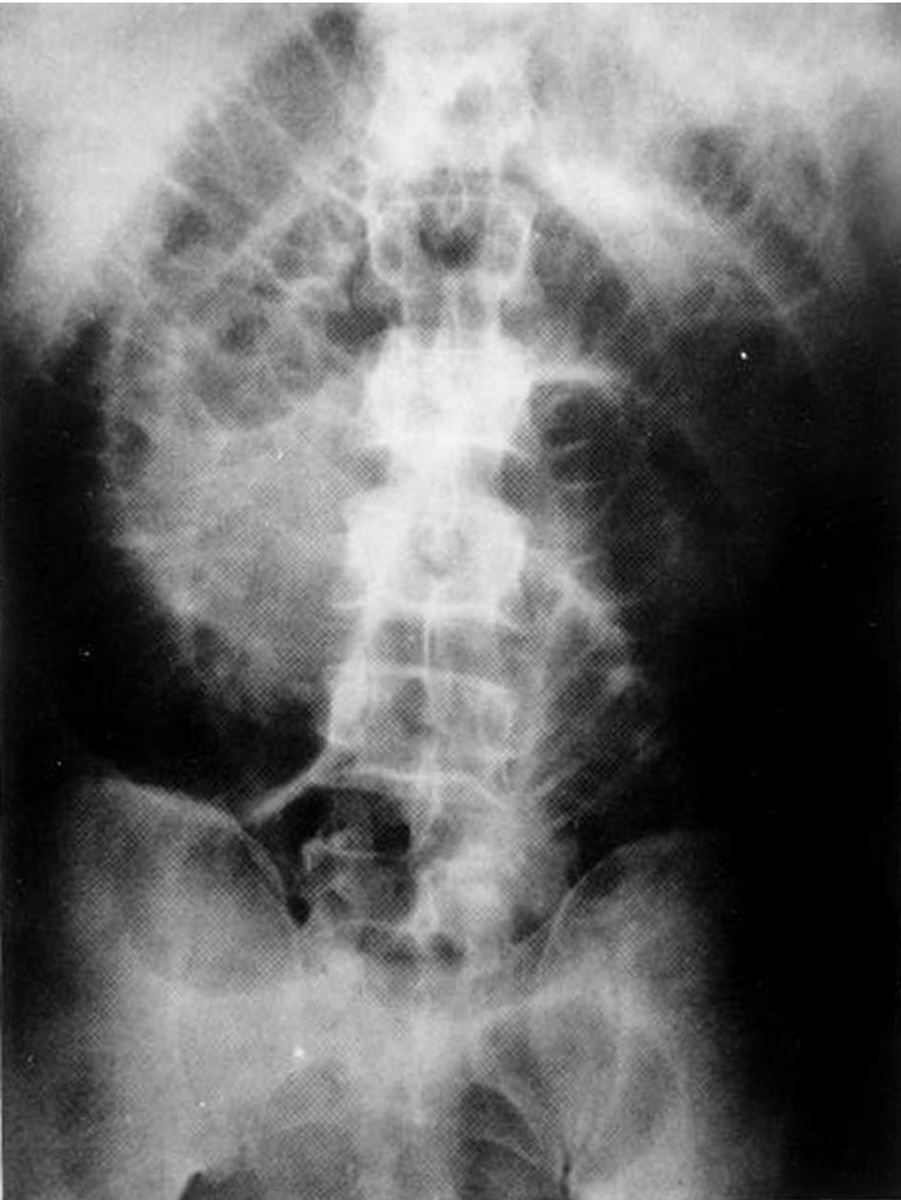

根据肠结石的混入成分,引起梗阻的肠石可分为3种:①真性肠石:一般是由肠道黏膜上皮、小型粪石、果核及其他异物等组成一个核心,经无机盐的沉积而形成结石。②药物性肠石:是因为长期口服含钙、磷、镁等的药物后在肠道内形成的不溶解性硬块。③混合性肠石(植物毛粪石):由食入的某些水果、蔬菜或吞食毛发后形成的,尤其食入未成熟的水果更易形成。

引起肠梗阻的结石中,以植物毛粪石较为多见。其中又以柿子形成的植物粪石最为常见。未成熟的柿浆和成熟的柿皮中含有鞣酸,鞣酸与胃酸接触后形成胶状的聚合物而沉淀,并不断吸附植物纤维成为团块,再经含钙、磷、镁等的无机盐沉积即形成肠石。食入柿子的量越多越易形成。毛粪石多见于精神失常者吞食了自己或他人、动物的毛发、树叶纤维、羊毛外衣等,较多的毛发可随胃肠蠕动而拌缠成发球,从而形成一个坚固孤立的团块。亦有报道胃肠吻合线部分脱落并以此为核心形成结石致肠梗阻的。有胃手术史者,如胃次全切除BillrothⅡ式吻合,迷走神经切断、幽门成形术等更易形成结石。Michael报道的113例胃肠石中,106例曾作过胃部手术。其原因是胃手术后,胃蠕动缓慢、排空延缓,使得胃内容物与胃酸接触的时间较长,容易形成胃石,尤其是食柿子后。胃手术后,尤其BillrothⅡ式吻合术,由于吻合口较大,在胃内形成的胃石更易进入小肠而引起梗阻。在肠道憩室处及肠狭窄的近端也容易形成肠石。